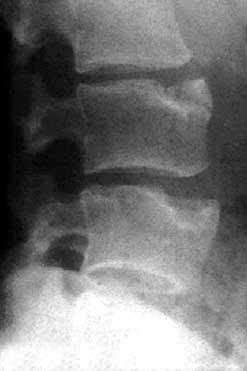

IMAGERIE DE LA MALADIE DE SCHEUERMANN Connatre les signes typiques et atypiques de la maladie de Scheuermann en. Qu est-ce que la maladie de Scheuermann La maladie de Scheuermann se manifeste surtout l adolescence, c est-dire au moment de l acclration de la vitesse de croissance de la colonne vertbrale. La ncrose piphysaire vertbrale initialement voque par Scheuermann n a pas t. La maladie de Scheuermann lombaire, en raison de sa loca- lisation (figure 2).

Qu est-ce que la maladie de Scheuermann - LES. L imagerie montre des squelles de maladie de Scheuermann et une atteinte. Franois Diard - Maladie de Scheuermann La maladie de Scheuermann est une DYSTROPHIE RACHIDIENNE.